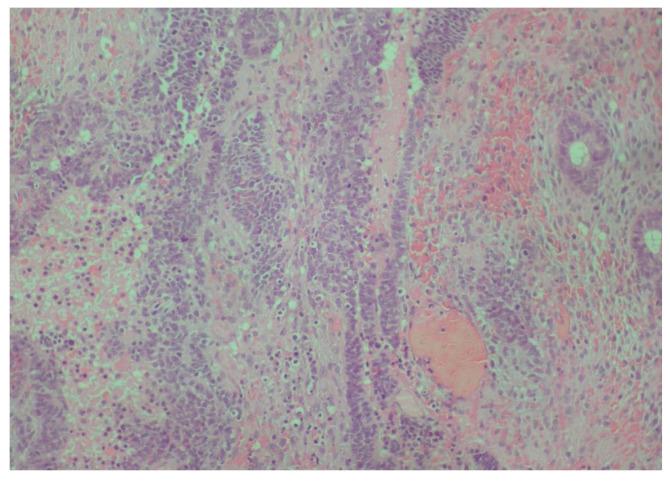

一名6岁男性患者被转诊至希腊塞萨洛尼基亚里士多德大学健康科学学院牙科学院口腔医学/病理学系的研究生诊所,因为他的儿科牙医在常规检查中发现牙齿#75远中处有一个外生性口腔内肿块。首次组织病理学检查显示为牙龈肿瘤,归类为小圆蓝细胞瘤,与釉质瘤样尤因肉瘤(ALES)更为相似,与滑膜肉瘤的相似性较小。第二位病理学家检查了相同的组织标本,并提示极罕见地存在未成熟恶性畸胎瘤。化疗后,切除了畸胎瘤剩余部分及相邻的牙齿#75,组织病理学检查显示为成熟畸胎瘤。